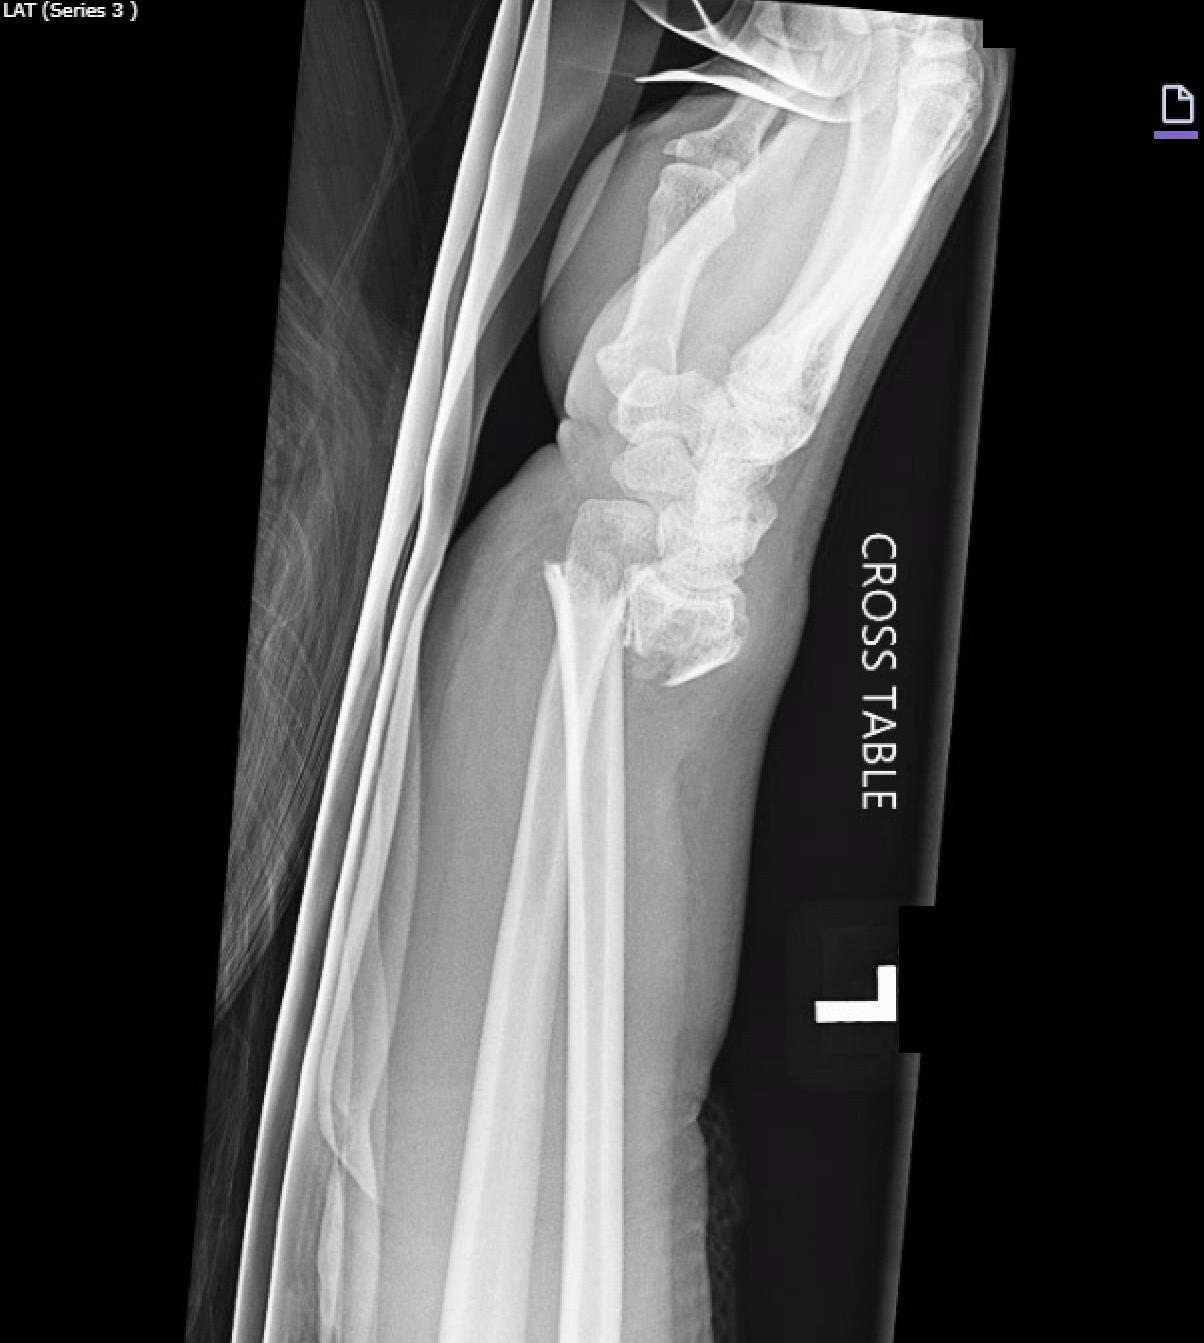

• Average age was 55 years, median follow-up was 24 months, and the most common use was in comminuted (92%) intra-articular (92%) distal radius fracture caused by fall (58%), or motor vehicle collision or motorcycle collision (27%). A minority of patients had open fractures (16%) and most were cases of polytrauma (65%). Median time from placement to DBP removal was 17 weeks (mean, 119 days). At final follow-up, mean wrist ROM was 45° flexion, 50° extension, 75° pronation, and 73° supination. Mean DASH score was 26.1, and mean QuickDASH score was 19.8. The overall rate for any complication was 13%; the most common was hardware failure (3%) followed by symptomatic malunion or nonunion (3%), and persistent pain after hardware removal (2%).

• Dorsal bridge plating was found to be used most commonly in intra-articular, comminuted distal radius fractures with overall functional wrist ROM, moderate patient-reported disability, and a 13% complication rate at follow-up.